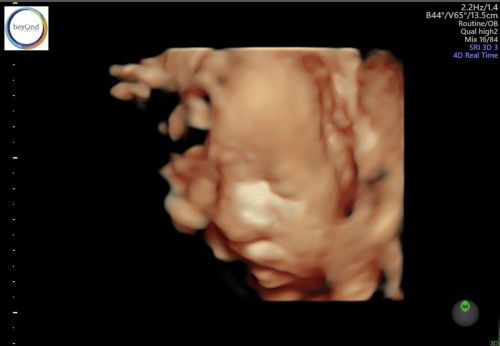

Bayi sungsang dan terlilit tali pusat saat 32w

Halo moms. Mau tanya, apakah disini ada yang pengalaman baby nya terlilit tali pusat 1 kali dan posisi sungsang frank breech? (bokong janin berada di bagian bawah dan tungkainya berada di bagian atas hampir menyentuh telinga). Saya tidak masalah dengan persalinan cesarean, namun baca2 di google katanya bayi beresiko cacat lahir atau gangguan kecerdasan kalau posisinya dia begitu 😭 So far beratnya normal kata dokter 1.600gr usia 32w. Mohon masukannya ya mom, saya takut sekalj bayi saya cacat, sampai sekarang usg 4d pun tidak terlihat jelas mukanya karena tertutup kaki 😣